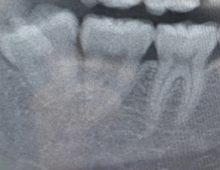

- 1.パノラマレントゲン

全体の口腔内のレントゲンになり上下の歯の位置や配置、虫歯有無や顎の骨を一度に評価することが出来ます。初めて受診される患者様や前回のレントゲン撮影から1年以上経った患者様には口の全体写真の撮影をお願いしています。